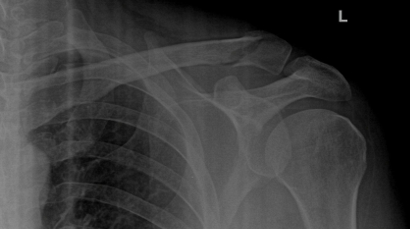

Displaced Clavicle Fracture with Butterfly Fragment